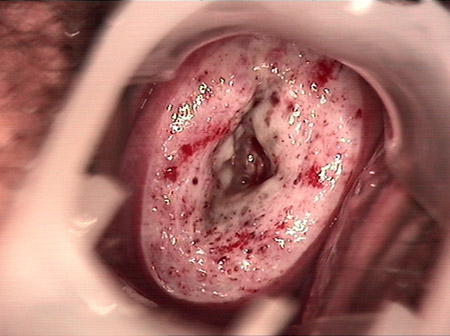

婦科leep錐切手術(shù) CIN2-3

• CIN 2-3 修復(fù)后CIN 2-3 修復(fù)后